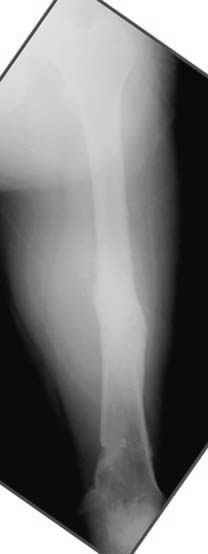

5:24 Рентгенограмма таза, вызывают врача ортопеда (снимок N1), его диагноз: закрытый переломо-вывих правого тазабедренного сустава, получает добро на закрытую репозицию в приемном отделении

N 2

7:30 начало операции, больной на спине, попытка репозиции после анестезии N3, укладка больного на боку, доступ Kocher- Langenbeck, состояние седалищнего нерва около 2.5см кровоподтек, через joistick головка бедра приподнята, освобовождение сустава, фрагмент заднего края более 3х4 см репонирован на свое место. После промывания

сустава, репозиция вывиха (N4), фиксация фрагмента 2.7(4) мм шурупами и допольнительно реконструктивной пластиной на 8 дырок, фиксация 3.5мм шурупами проксимально и дистально.

Интраоперционные N5 косая запирательная и N6 подвздошный снимок

11:50 больной в послеоперационной, рентгенограмма N7, компьютерная томограмма в тот же день N8-10